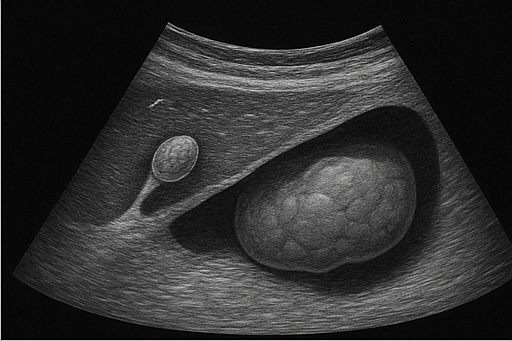

- 담낭 용종: 담낭 내부에 생긴 작은 돌출물로, 대부분 양성이지만 크기에 따라 추적 관찰이 필요합니다.